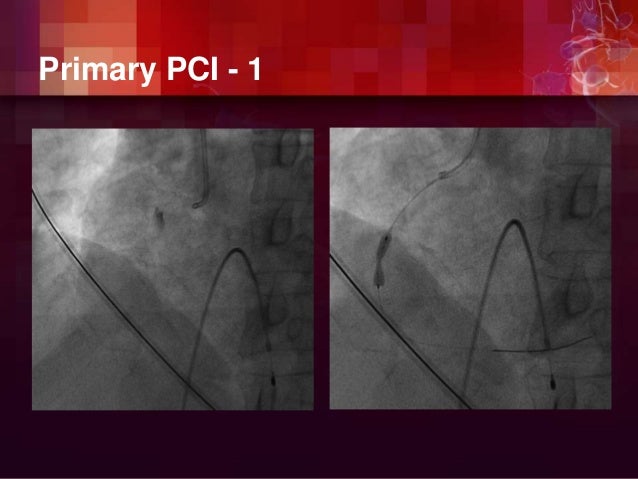

Ischemic Heart Disease

Pathophysiology of ischemic heart disease.